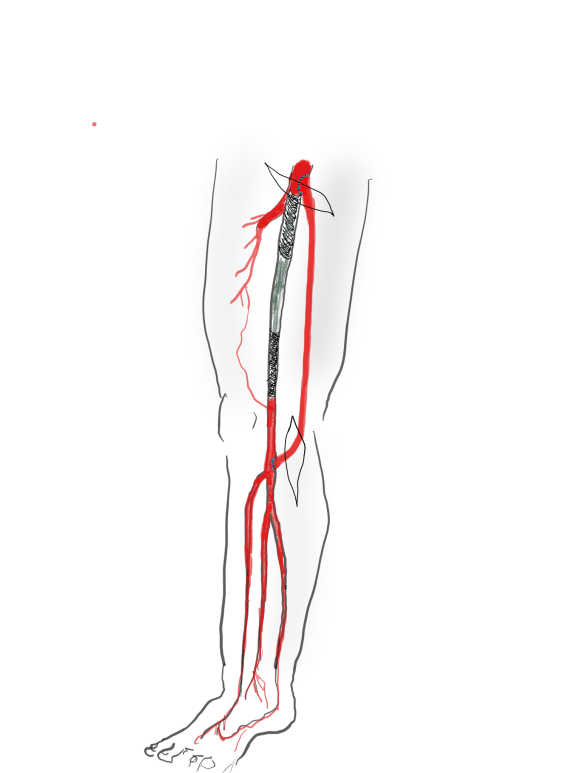

Like Mid-Century Modern Design furniture, surgeons in my cohort are sought after by hospitals and practices for being able to let a hospital do more. What do I mean? A urologist resecting a kidney with a renal vein tumor thrombus extending into the inferior vena cava needs to have someone expose, extract, and repair the vena cava. A gynecologist debulking retroperitoneal metastases needs to be able to call for help when part of the aorta needs to go with the tumor. Cardiac surgeons need to be able to place ECMO cannulas in imaginative locations and not lose extremities in the process. A thoracic surgeon resecting a Pancoast tumor needs a vascular surgeon to repair the subclavian artery and vein. An orthopedic surgeon resecting a spindle cell tumor from the thigh needs help reconstructing the femoral artery and vein. And so on. We are safety net, the fire brigade, the SEAL team, and unfortunately many hospitals understand only when their last fully trained, full service vascular surgeon retires.

Vascular surgeons are a keystone species in a hospital’s ecosystem. When wolves were reintroduced to Yellowstone, it was noticed that decades later the forests returned to their ancient glory, that wetlands flourished breeding fish and insects and small mammal species, and the secondary predators that feed on them, and many missing bird species returned. Vascular surgeons capable of operating on the whole body as well as intervening on the whole body are increasingly a missing element in a hospital. And many of us chose to go missing -into our private endovascular suites and vein centers because it often does not pay to go do a 5-hour bypass when you can do three femoral angioplasties for claudication in the same time. Reading 10 carotid ultrasounds is easier on the back and more renumerative than a carotid endarterectomy. And I am not judging -it is a rational choice that is framed by the way healthcare is reimbursed.